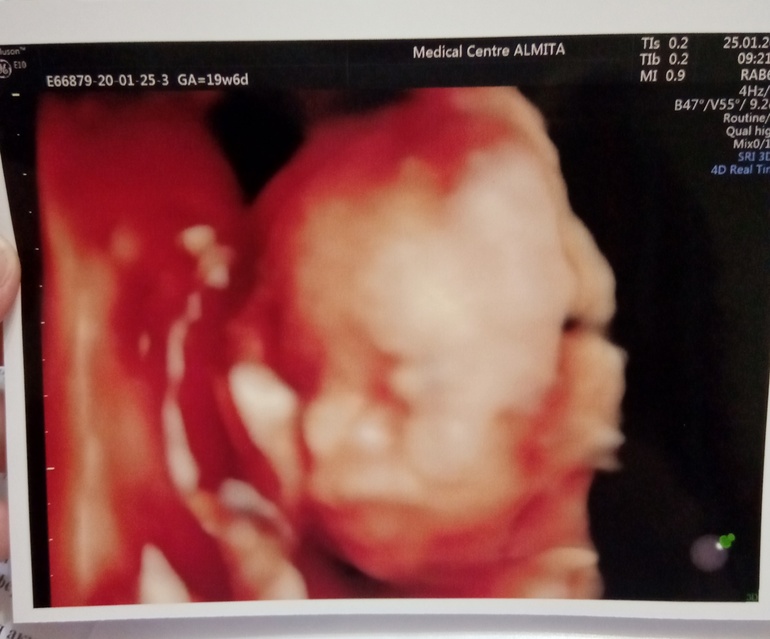

Итак, сходили мы (Я, муж и вторая доча) на экспертное УЗИ в "Алмиту", к доктору Дегтяреву. В кабинете 2 стула для родственников, огромный экран. Сразу же посмотрели пол, видимо, чтобы не приставали и дали спокойно работать 😁 Вот, говорит, ягодичка, вот ещё одна. А это бантик 😆

До сих пор улыбаюсь и смотрю на ее фоточку. Хоть и страшненькие виды, но черты четко видны. И уже понятно точно, что губки папины, 1 в 1. С носиком мы ещё спорим))))